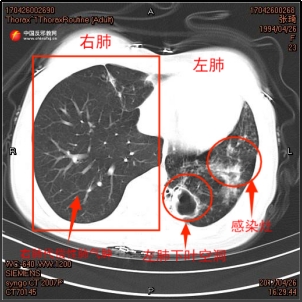

Bei der zweiten Tuberkulose-Diagnose im April 2018 bestätigte eine Sputumkultur von Zhang Qi eine begleitende Aspergillus-Infektion. Der damalige Stationsarzt Zhang Yang erinnerte sich an die Behandlungsschwierigkeiten: „Bei Zhang Qi wurde zum zweiten Mal eine rezidive, resistente Tuberkulose diagnostiziert. Wir erstellten einen gezielten Behandlungsplan und fügten orale Antimykotika hinzu.“ Die während der Behandlung mehrfach angefertigten CT-Aufnahmen des Brustkorbs von Zhang Qi dokumentierten ebenfalls die Verschlechterung ihrer linken Lunge. Die Höhle im linken Unterlappen von Zhang Qi vergrößerte sich allmählich, der Lungenlappen atrophierte, und die Infektion verstärkte sich zunehmend.

▲ links: CT-Aufnahme von Zhang Qis Brustkorb vom April 2017;

rechts: CT-Aufnahme von Zhang Qis Brustkorb vom April 2018